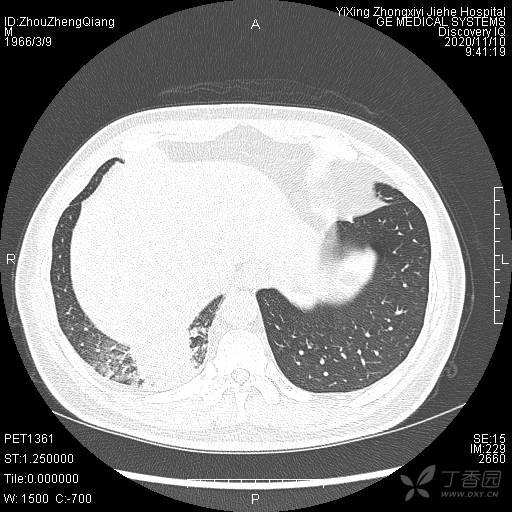

辅助检查:CT提示:右下肺占位伴周围炎症,CA待排,右侧少许胸腔积液。

临床诊断:右肺癌?待进一步检查。